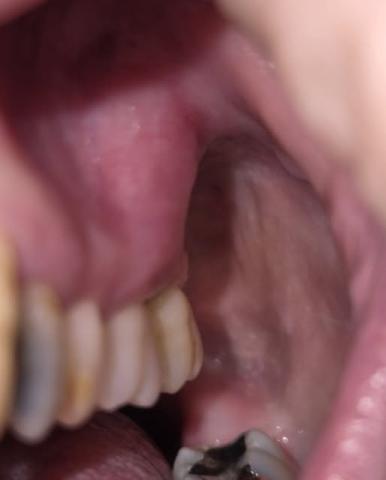

Based on the image provided, there are several significant dental health concerns that require immediate professional attention:

Gross Caries (Severe Decay): The lower molar (bottom right of the photo) shows a large, dark cavitation covering most of the occlusal (biting) surface. This indicates extensive tooth structure loss.

Likely Pulp Exposure: Given the depth of the dark area on the lower molar, the decay has likely reached the pulp (nerve) of the tooth.

Gingival Recession & Inflammation: The gums surrounding the upper teeth appear retracted, and there is visible redness/inflammation, suggesting periodontal (gum) disease.

Heavy Calculus/Staining: There is significant buildup on the lingual (inside) surfaces of the upper teeth, which harbors bacteria and contributes to bone loss.